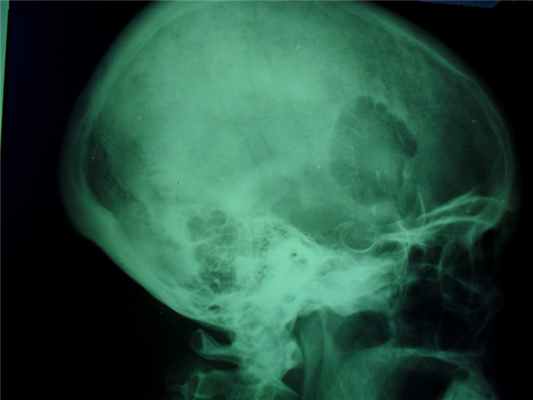

Прямая рентгенограмма таза и тазобедренных суставов.

Определяется резкая деформация тазового кольца. Правый тазобедренный сустав в норме. Выраженные изменения в левом тазобедренном суставе: суставная впадина углублена, суставная щель не прослеживается, головка деформирована с множественными очагами деструкции. Регионарный остеопороз, атрофия бедренной кости. Левосторонний туберкулезный коксит.